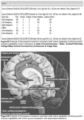

- Forward equation targeted EEG brain region monitoring including circadian clock function incorporates forward equation source localisation such as (but not limited to) monitoring and derivation of associated measures relating to the subject/patient's natural circadian rhythm, including (but not limited to monitoring associated brain regions (i.e. suprachiasmatic nucleus (circadian clock) regions) applicable to circadian EEG cycle signals (such as for determination of circadian clock cycle for subject/patient), Whereby in one embodiment example based on configuration of EEG sensor monitoring system (i.e.

- the present invention can determine optimal EEG signal processing (i.e. adapting frequency, phase and/or amplitude of sensor signals) applicable to sensor monitoring system's specific electrode location (i.e. per Somfit) in order to emulate location of brain regions (i.e. suprachiasmatic nucleus (circadian clock) regions) applicable to circadian EEG cycle signals (such as for determination of circadian clock cycle for subject/patient), and/or consciousness switch region (i.e. thalamus), or other brain regions (i.e. but not limited to Figure 66 source localised regions).

- brain regions i.e. suprachiasmatic nucleus (circadian clock) regions

- circadian EEG cycle signals such as for determination of circadian clock cycle for subject/patient

- consciousness switch region i.e. thalamus